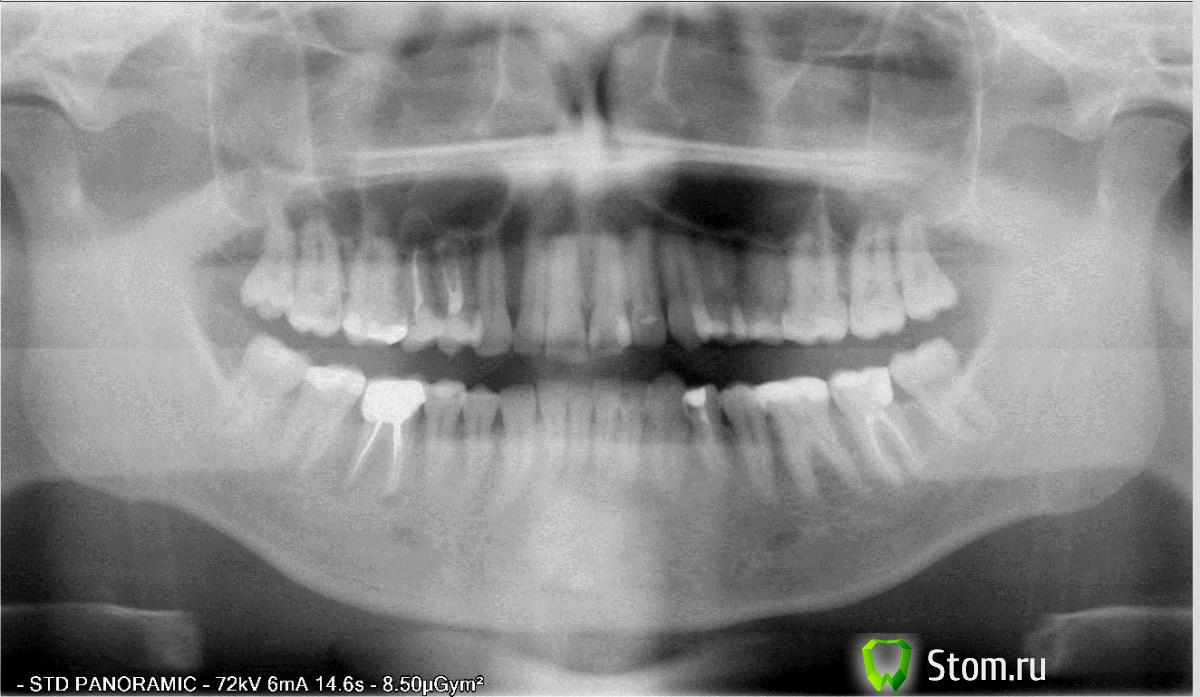

Barabulkahse Опубликовано 22 марта, 2012 Поделиться Опубликовано 22 марта, 2012 Мне 31 год, в 2007 был пульпирован зуб и поставлена коронка (в нумерации зубов не силён на снимке думаю всё понятно).По моему мнению коронка поменяла прикус и мешала с самого начала.Зуб стал побаливать - скажем так напоминать о себе не сильные боли чуть ноющие в основном по ночам - утром всё хорошо!Посетив клинику (где мне ставили коронку в 2010) сказали, что ничего серьёзного антибиотики если проёдут то всё ок.Подозрение было на сильное сжатие челюсти и травму.Через год ситуация повторилась - посетил ту же сеть клиник но другого врача .... ничего серьёзного опять не обнаружили но сказали, что передонтит и десна кровотичит - парадонтолог провел некоторые манипуляции (чистку лечение и т.д.). И сказал что есть все предпосылки лоскутной операции но пока лучше с ней повременить посмотреть на результат чистки через пол года.Через год повторились боли ....решился на диагностику и исправления прикуса (смену части детских пломб ещё ртутно свинцовых и т.д.) - боли прошли.Последние изменение смена пломбы над коронкой ...прикус изменился и давление на коронку опять изменилось на следующий день зуб снова напомнил о себе.Есть небольшие изменения у корня зуба....рекомендуюи сделать резекцию.Слово РЕЗЕКЦИЯ мне не нравится жду советов Боли не сильные просто постоянные в основном вечером и только когда холодно на улице. Боли идут 1 -2 дня.По ночам во сне сжимаю зубы и скриплю (опять же со слов). Ссылка на комментарий

Barabulkahse Опубликовано 22 марта, 2012 Автор Поделиться Опубликовано 22 марта, 2012 Вот зуб отдельно вырезал снимок только один прицельного нет. Ссылка на комментарий

dok1 Опубликовано 22 марта, 2012 Поделиться Опубликовано 22 марта, 2012 У вас , выражаясь по простому, очаг хронической инфекции не верхушках корней.Если это действительно от завышающей коронки, то её следует обязательно пришлифовать до очень ослабленного контакта с верхними зубами, или вообще вывести из прикуса(контакта).Кстати, зуб не подвижен? перелечить каналы скорее всего не удастся, т.к. нужно будет извлеч вкладку, которая , скорее всего "намертво" зацементирована в корень.Резекции не бойтесь.Это небольшое хирургическое вмешательство, которое сохранит вам зуб, т.к. будет устранён очаг воспаления на верхушках корней. Ссылка на комментарий

Чиффа Опубликовано 23 марта, 2012 Поделиться Опубликовано 23 марта, 2012 Резекции не боюсь .3 диагноза - разные врачи разные клиники разный диагноз, чему верить то?!?!?1. Завышение прикуса.2. Пародонтит.3. Резекция.Всё лечится по разному Две ваши проблемы-завышение коронки по прикусу и воспаление вокруг корней зуба(периодонтит)-друг друга НЕ взаимоисключают. Очаг хронической инфекции-это очень плохо, с ним надо бороться. Гарантийный случай в данной ситуации-удаление этого зуба и установка импланта.Негарантийно нужно пришлифовать коронку зуба, чтоб не мешала по прикусу, и сделать резекцию.Кстати, если коронка мешала по прикусу с самого начала, почему не требовали у врача переделки или устранения дискомфорта? Ссылка на комментарий

Чиффа Опубликовано 23 марта, 2012 Поделиться Опубликовано 23 марта, 2012 Чрезмерная перегрузка зуба приводит к воспалительному процессу в периодонте. И это не считая того, что каналы могли быть запломбированы некачественно.Как только Ваша имунная система ослабевала, происходило обострение хронического воспалительного процесса, и начинались боли. Ссылка на комментарий